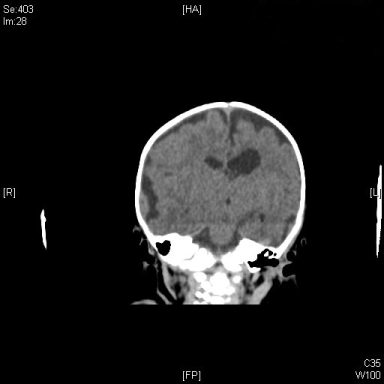

CT brain

A large intraparenchymal hemorrhage in the left temporoparietal lobes, diffuse hypodensities of cerebral parenchymal. Multiple extra-axial fluid collection likely subacute hemorrhage along convexity of both cerebral hemispheres (Figure 2).

Figure 2: CT image of infant head, a coronal view demonstrate large intraparenchymal hemorrhage located at the left temporo-parietal lobes diffuse hypodensities of cerebral parenchymal. View Figure 2